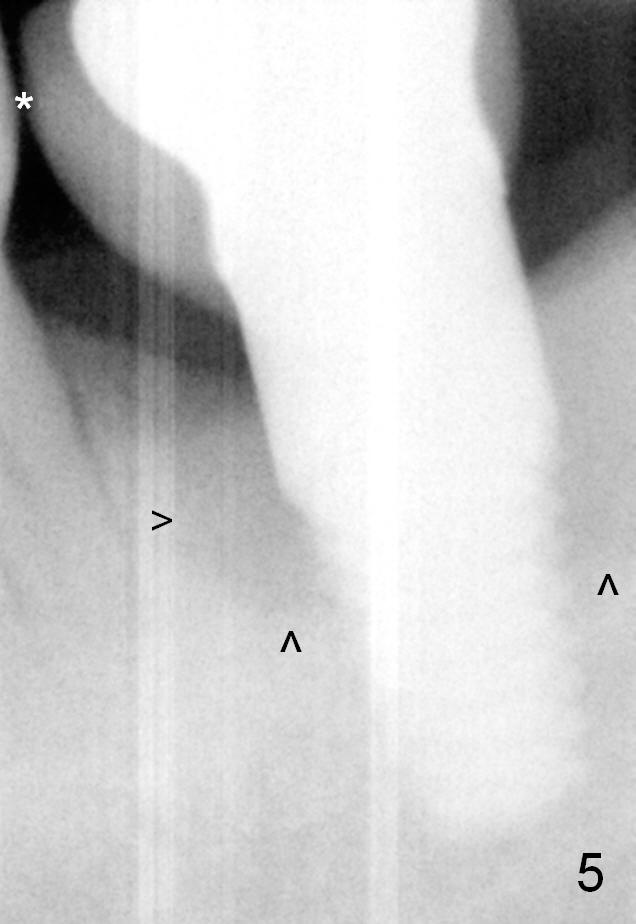

In spite of history of chronic periodontitis, the patient does not return for regular maintenance. There appears mild bone loss around the implant 2 years 3 months post cementation (Fig.4 ^). The bone loss appears to increase, accompanied by loose contact with the neighboring tooth 3 years 10 months post cementation (Fig.5 *, compare to Fig.4).